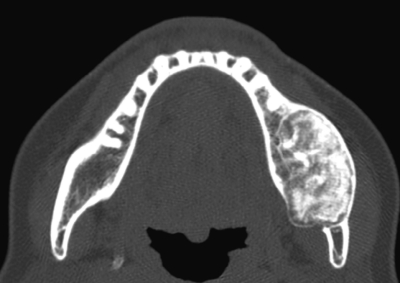

35 歳の女性。下顎左側臼歯部の膨隆を主訴として来院した。病変は骨様硬で、疼痛や下唇の感覚異常はない。初診時の口腔内写真、エックス線画像、CT及び生検時の H-E 染色病理組織像を別に示す。

診断はどれか。1つ選べ。